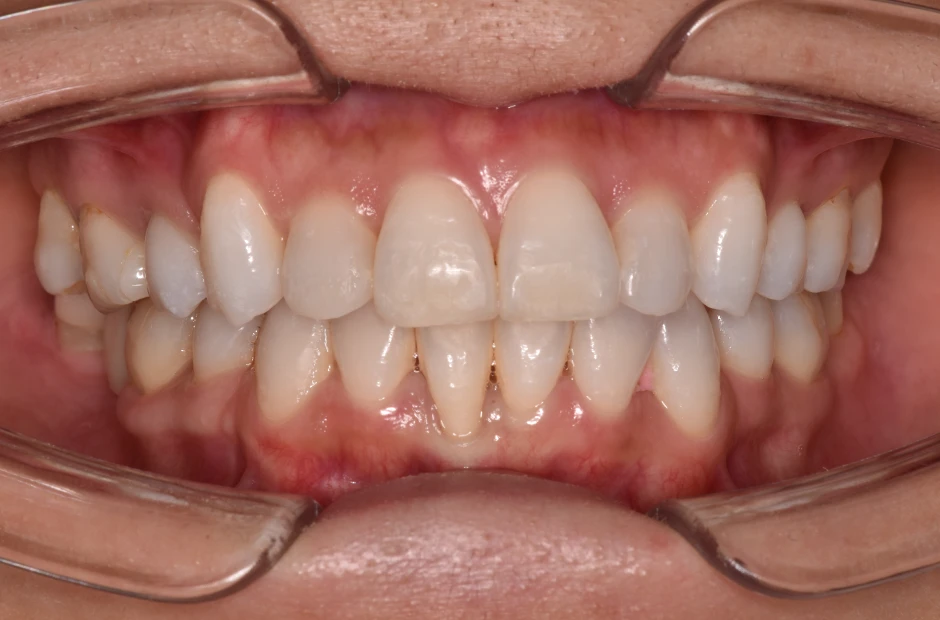

反対咬合

| 診断名・主訴 | 下顎前突、叢生 |

|---|---|

| 年齢・性別 | 23歳・女性 |

| 治療期間・回数 | 3年 |

| 治療に用いた主な装置 | 上顎5,5 下顎4,4 |

| 抜歯部位 | 舌側矯正 |

| 治療費 | 100万円(税抜) |

| リスク・副作用 | 装置による違和感・疼痛・歯肉退縮・歯根吸収・虫歯のリスクなど |

治療前

治療中

治療後